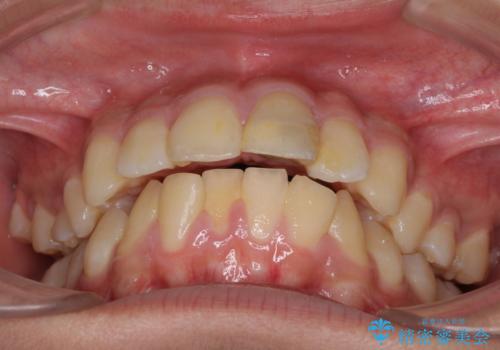

- 口元の突出感を気にして来院された患者様です。

上下前歯が著しく前突している状態であったので、上下左右の第1小臼歯4本を抜歯し、ワイヤー装置にて矯正治療を行うこととしました。

舌の突出癖により、前突になったと考えられたため、舌のトレーニングをしっかりと行うよう指導しました。